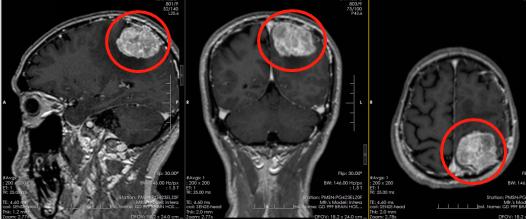

▲术前头颅MRI示:左侧顶部颅骨内板下团块状长T1稍长T2异常信号,FLAIR序列呈稍高信号,增强后明显强化,其内示多发细小血管影,病灶范围约44mm×49mm×42mm

▲头颅MR灌注检查提示:左侧顶部占位病变CBF图伪彩图红色改变;头颅CTA提示:左侧顶部占位性病变血供丰富